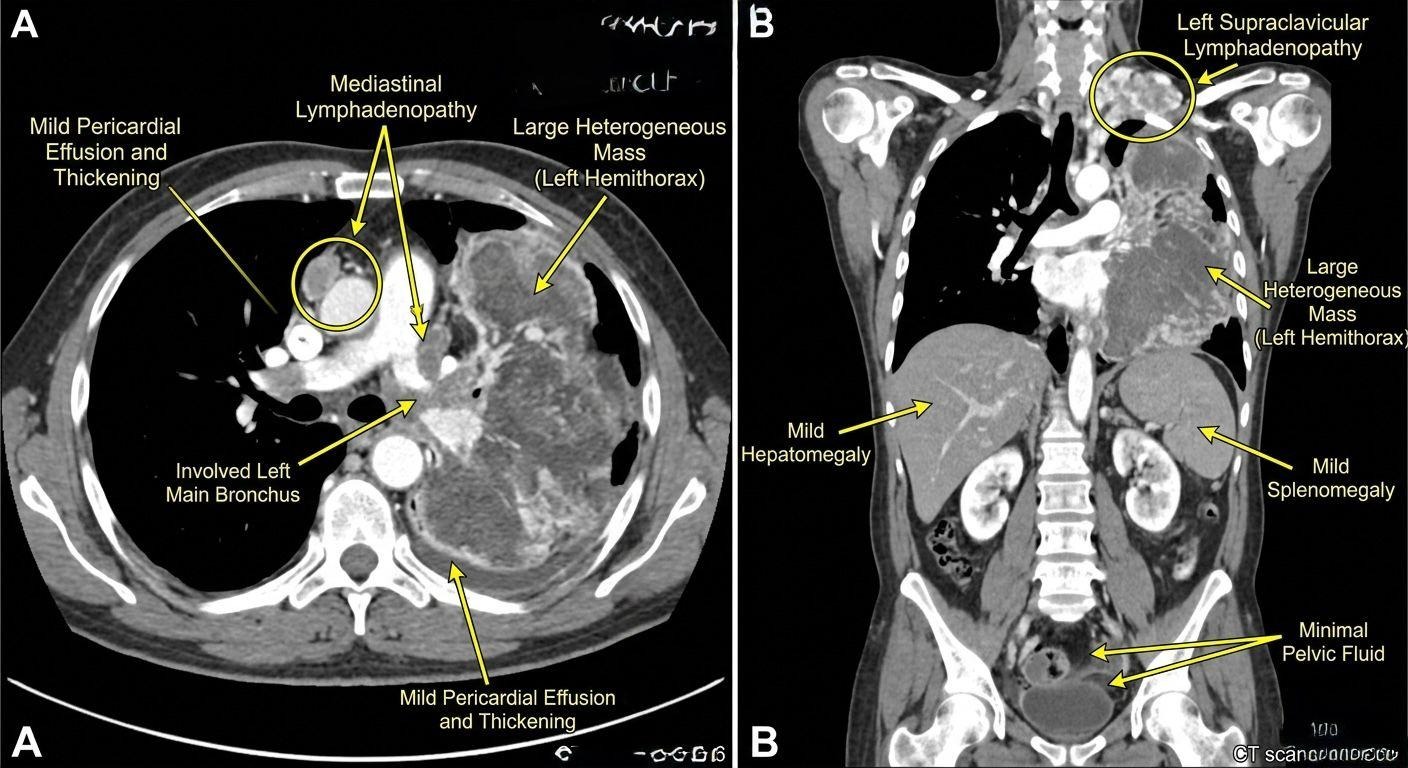

Anatomical Imaging

Contrast enhanced imaging demonstrated a large heterogeneous mass occupying the left hemithorax with bronchial involvement, mediastinal and supraclavicular lymphadenopathy, pericardial effusion, hepatosplenomegaly, and minimal pelvic fluid.

Fig. 2: Contrast-enhanced computed tomography of the chest, abdomen, and pelvis demonstrates a massive, multilobulated, heterogeneously enhancing soft-tissue mass occupying the entire left hemithorax, with internal low-attenuation areas suggestive of necrosis or hemorrhage, indicative of aggressive tumor biology. The lesion shows direct encasement and luminal narrowing of the left main bronchus (as marked), favoring true airway invasion. There is extensive mediastinal and left supraclavicular lymphadenopathy, consistent with advanced nodal dissemination. Mild pericardial effusion with associated thickening suggests early serosal involvement. Abdominal findings include mild hepatomegaly and splenomegaly (highlighted), likely reflecting systemic or reticuloendothelial response in the absence of focal lesions, along with minimal pelvic free fluid. The contralateral lung remains free of metastasis.